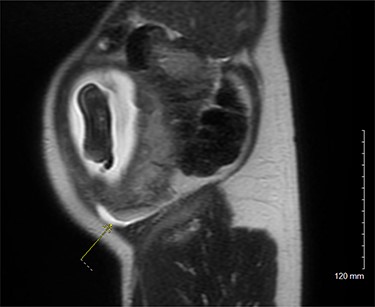

On examination, the patient was a thin woman with a gravid uterus. She was very tender to palpation across the right lateral aspect of her abdomen, extending superiorly from the anterior superior iliac spine. Laboratory data were significant for a leukocytosis with a neutrophilic predominance. An ultrasound was obtained, but the technician was unable to visualize the appendix. The patient continued to have severe pain on the right side and an abdominal magnetic resonance imaging (MRI) was ordered. The attending radiologist reported a dilated appendiceal tip at 1 cm with surrounding inflammatory changes and free fluid, consistent with tip appendicitis (Figs 1 and 2). The cecum was noted to be superior to its normal position, with the right colon folded on itself, coursing down from the hepatic flexure before turning back upwards. The location of the appendix on the MRI correlated with the patient’s location of maximal pain and tenderness.